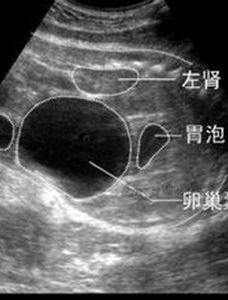

3、超聲檢查示腎實質占位性病變,多為強回聲的腫塊。

本組22例,男10例,女12例,年齡16~67歲,平均46.4歲。腫瘤位於右側9例,左側13例。腫瘤大小0.4cm×0.6cm×0.7cm~13.5cm×14.3cm×15.2cm,病程1個月~7年。主要臨床症狀為腰部不適、脹痛、包塊、出血性休克等。22例均行KUB加IVP和CT檢查,2例行MRI檢查。IVP表現為正常或提示腎盂腎盞受壓變形;B超檢查多表現為強回聲光團,也表現為混合回聲,診斷準確率為86.4%(19/22);CT平掃多表現為圓形或類圓形低密度或極低密度病灶,病灶位於腎實質內或突出於腎輪廓外,診斷準確率為90.9%(20/22)。

腎錯構瘤B超結合CT診斷腎錯構瘤有重要價值,隨著超聲、CT和MRI的套用,腎錯構瘤的發病率有所增加,術前診斷準確率也有所提高。腎錯構瘤與腎細胞癌的影像學鑑別要點在於腎錯構瘤含有較多脂肪成分而正常腎及腎細胞癌組織極少或沒有,腎錯構瘤在B超圖像中表現為強回聲光團,偶然可見混合性低回聲。CT顯示比超聲圖像更敏感,CT值於小-10Hu,因此,典型的腎錯構瘤不難診斷。MRI檢查時,T1加權像較低,T2加權像又極高。IVU主要了解雙腎功能情況,對於評估腎功能不良患者是否進行手術以及手術方式的選擇具有重要作用。